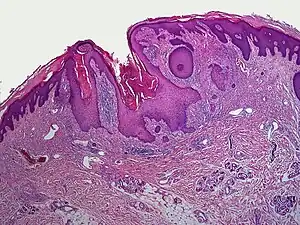

| Dilated pore of Winer |

A dilated pore, also known as a dilated pore of Winer, is a cutaneous condition characterized by a solitary, prominent, open comedo on the face or upper trunk of an individual.[1]: 675 Louis H. Winer is credited with discovering the dilated pore. [2][3]